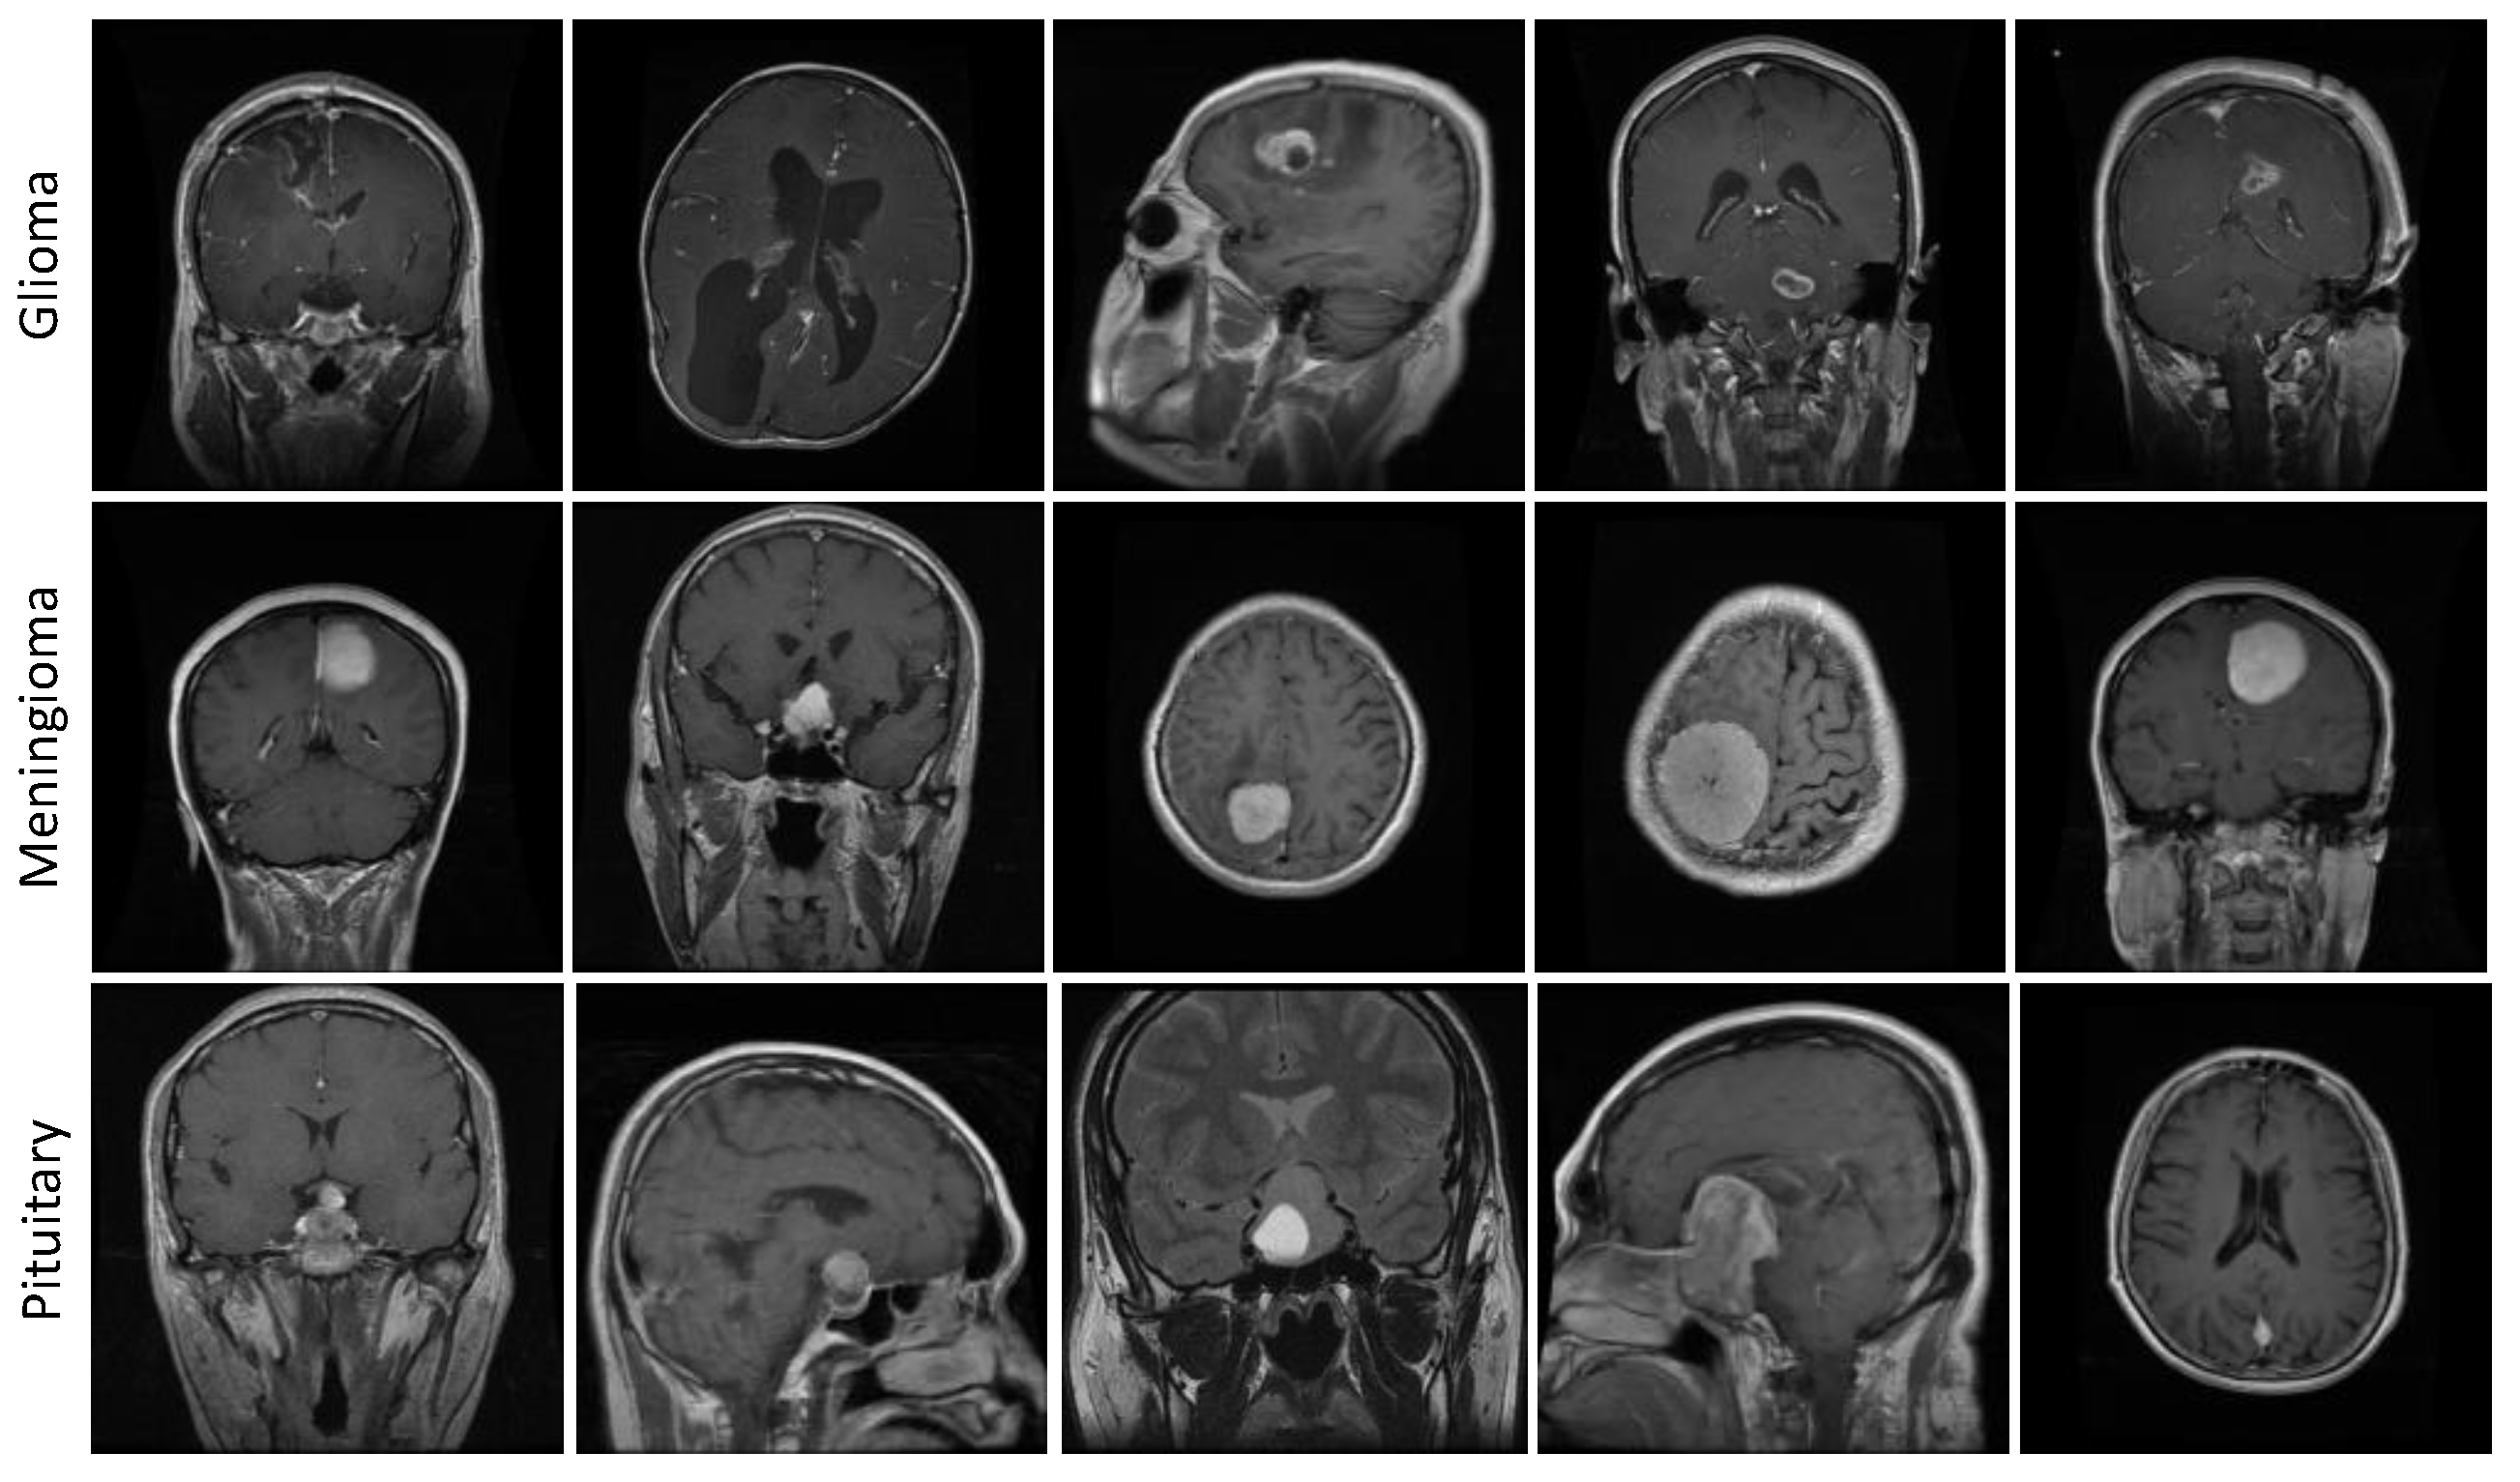

3.5.2. Figshare Dataset